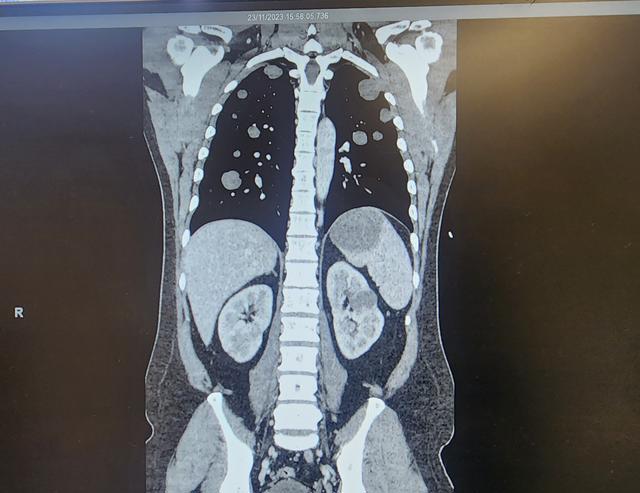

Update: Had chest scan and doc visits this morning.

2nd day of chemo. Started 2 hours ago. Lot of fluid in and around his right lung so if they need to, they will put a breathing tube down his throat and continue to give him chemo through his lure. Hes finding it hard to breathe still so the oxygen levels are stable atm to help him. No sleep during the night now I feel like my eyeballs are popping out of my head. MyLove kept trying to fall asleep but got scared that he wouldnt wake up so hes just as tired as me. Hoping for a better day today and that it doesnt come to needing a tube. Couple more hours of chemo yet. 🤞